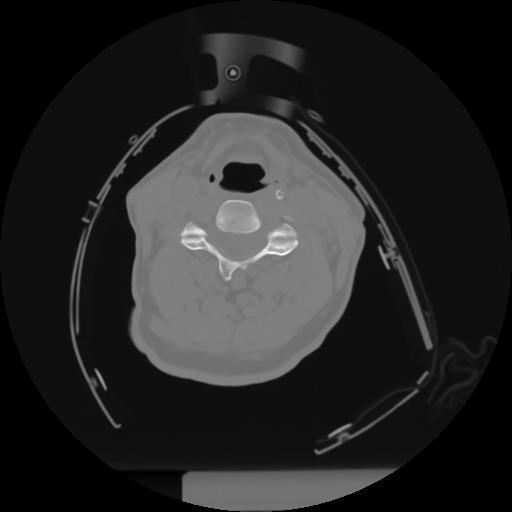

10 P.BLANDAS,,Axial,2.0,P.BLANDAS,,